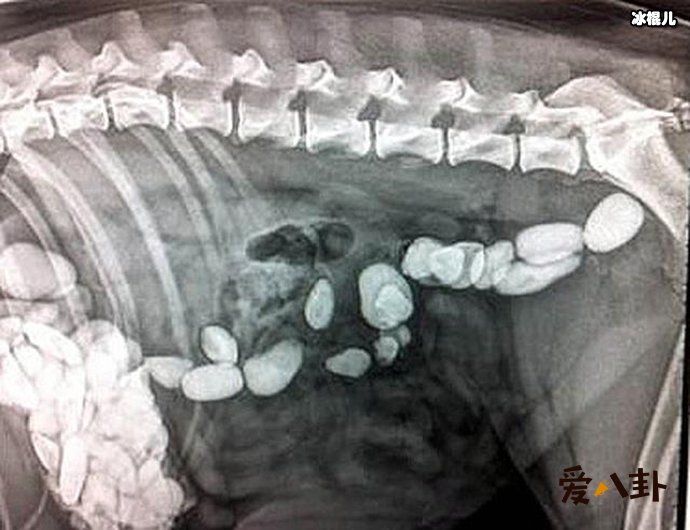

但是小柯的回答让医生也吓了一跳,他回答称:因为自己与女朋友吵架,在吃金项链之前,还赌气吃了200颗的褪黑素下去。这可让医生吓了一跳,马上安排给小柯做相关的检查,发现金项链已经到了肠子里了,而小柯也没有什么不舒服的地方。因此,医生表示金项链会随着大便一起排出,建议小柯在回家排便的时候注意看一下金项链有没有排出。